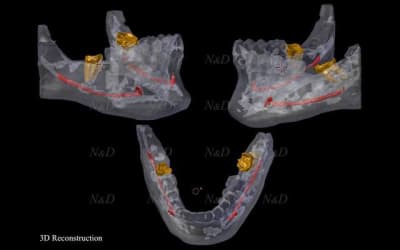

> voila comme promis une vidéo planif et guide entièrement faite avec blender sans utiliser meshlab

un petit test avec mon nouveau jouet

1) plâtre cône beam dans invesalius

2) cone beam vs cam3d

3) collage dans blender

4) résultat

toujours avec mon nouveau jouet, je n'avais jamais testé mais cela fonctionne parfaitement bien

plus besoin de faire couler le plâtre par le labo!!!

un scan ou un cone beam de l'empreinte suffit

très simple ensuite de préparer une provisoire